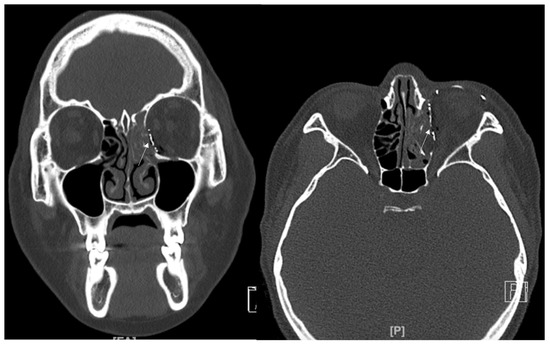

Figure 8. (A) A 29-year-old male patient came to our clinic with right eyeball swelling and ecchymosis caused by a direct trauma. The patient complained of pain and discomfort with eyeball movement. We surgically approached the inferomedial orbital wall fracture one day after the accident. After the subciliary incision, the fracture was exposed. (B) The titanium-reinforced porous polyethylene (TR-PPE) plate placed on the orbital floor using a single screw at the inferior orbital rim. The patient was discharged on postoperative day 2 with significantly improved pain and discomfort. The fracture sites were designated with white arrows. The titanium-reinforced porous polyethylene (TR-PPE) plate was placed on the inferomedial orbital wall using a single screw at the inferior orbital rim. (White arrow).

In this study, we excluded inferior wall fracture involving IOS. However, as shown in Figure 8, this inferior wall fracture with the involvement of IOS is also a good candidate for using titanium-reinforced porous polyethylene (TR-PPE) plates.